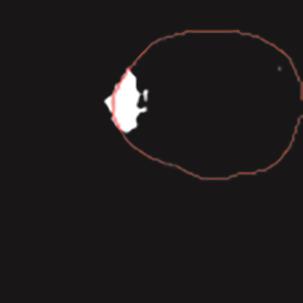

乳腺癌是全球女性最常见的恶性肿瘤之一,准确的病变分割对于乳腺癌的早期诊断与治疗具有重要意义。然而,由于病变形态的多样性以及超声成像机制的复杂性,现有基于深度学习的乳腺超声图像病变分割方法在分割准确性方面仍面临巨大挑战。为进一步提升乳腺超声图像中病变区域的分割精度,该文基于经典U-Net架构,提出了一种新型乳腺超声图像病变分割网络(CWSASKM-BBAM-Net)。首先,在网络中引入逐通道空间自适应选择核卷积模块(CWSASKM),根据不同通道的语义特征为每个空间位置自适应选择感受野大小,以增强多尺度信息的建模能力;然后,引入双向边界感知机制(BBAM),通过融合正向与反向注意力,对目标显著区域及其边界进行协同建模,同时逐步提升对非显著区域与病变区域的区分能力,以进一步强化边界信息的表达;最后,在3组公开乳腺超声图像数据集(BUSI、UDIAT和STU)上开展分割实验。结果表明:该方法在数据集BUSI上的杰卡德指数、精确率、召回率和Dice相似系数分别为71.97%、82.85%、81.40%和80.44%,较次优方法分别提升1.69、1.05、1.28和1.84个百分点;在数据集UDIAT上,这4项指标分别达到78.14%、88.31%、86.73%和86.10%,较次优方法分别提升了2.75、2.04、0.56和2.01个百分点;在外部数据集STU上,该方法也取得了优于其他方法的整体表现。实验结果表明,CWSASKM-BBAM-Net在乳腺超声图像分割任务中展现出更优的整体性能。